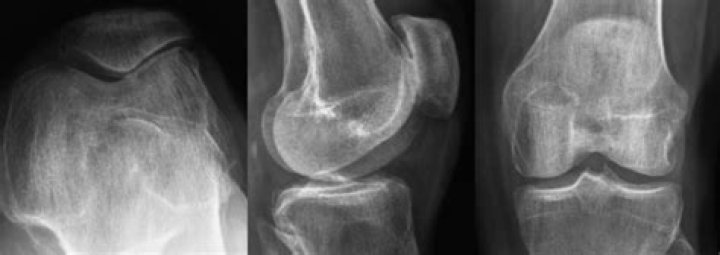

Because a torn meniscus is made of cartilage, it won't show up on X-rays. But X-rays can help rule out other problems with the knee that cause similar symptoms. MRI . This uses a strong magnetic field to produce detailed images of both hard and soft tissues within your knee.